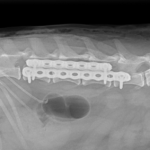

椎体固定術

10歳のワンコが後肢フラツキの精査のため、かかりつけの動物病院より画像診断と治療のために紹介受診されました。CT/MRI検査では第3腰椎の左側から脊柱管内に重度に浸潤し、脊髄の90%以上を圧迫する占拠性病変が確認されました。また椎体にも骨融解像が確認されました。姑息的ではありますが、腫瘍摘出により除圧することで神経学的機能回復に期待することと、今後の病期の進行に伴い椎体の不安定性が懸念されたため、2.0mmのTitanium Locking Plateを2枚用いて部分的にスタッキングさせると同時に4本のLocking Screwを用いて椎体固定術を実施しました。脊柱管内に浸潤し、脊髄を圧迫していた腫瘍はほぼ完全な摘出が可能となりました。術後すぐに歩行可能となり、良好な機能回復が得られています。今後は摘出した腫瘍の病理検査により追加の治療を決定します。